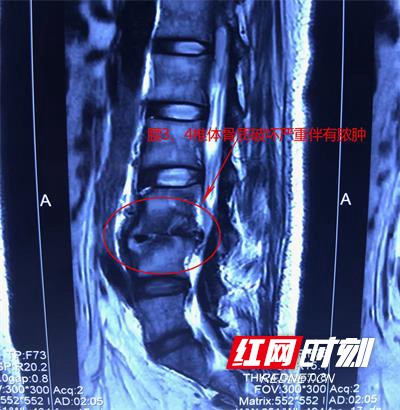

彭女士腰椎X光片。

医生检查发现,彭女士腰3、4椎体局部后凸,活动受限,有明显压痛,腰椎X光片、CT检查显示腰3、4椎体骨质破坏严重,伴有脓肿,确诊为腰椎结核。根据当前症状及影像检查结果,长沙骨质增生专科医院脊柱外科黄清明主任建议彭女士,在全身抗结核应用下进行手术治疗。经过12天的系统治疗,病情明显好转的彭女士已经能下床行走了。